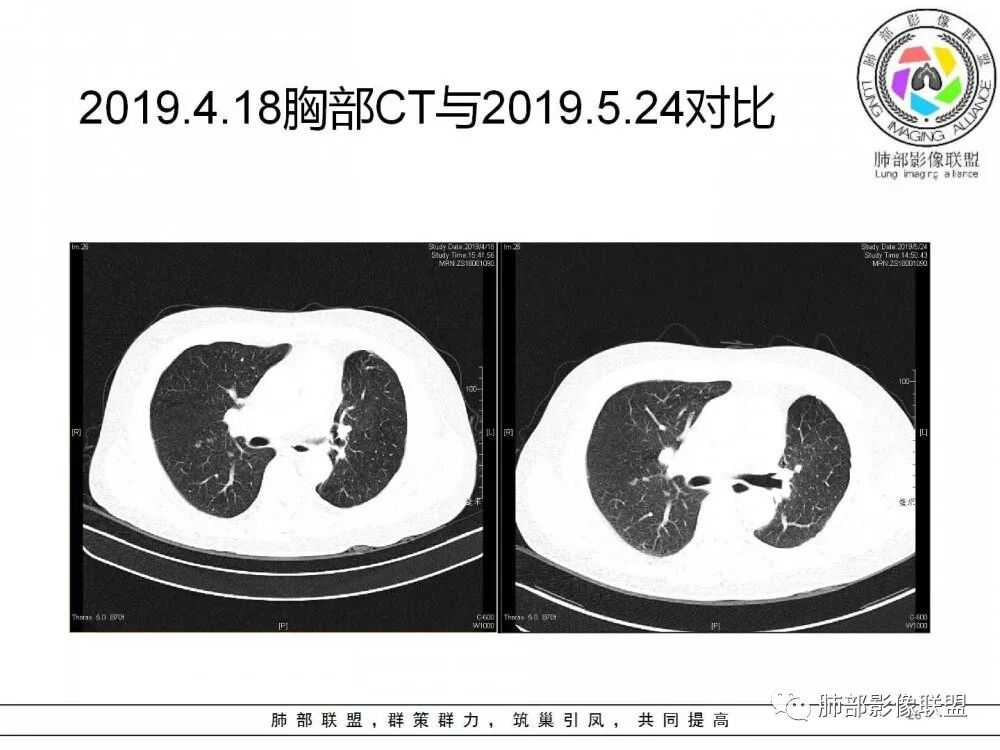

病灶从2月份就开始有,应该最早说是1月7号就有了,到3月13号稍微增大一点,到后面几乎没变化,到5月份好像稍微大一些,炎性应该是炎性,犹豫的是这个炎性到底什么病变呢?其实本没变化,它特点一个是在叶裂上,跟血管关系密切,但是病灶边缘稍收缩,病灶没有太大变化。

确实当时病人来了考虑转移可能,就测了基因,上了靶向药,两月变化不大

因为这个长轴似乎跟支气管走行一致的,其实治疗效果不是很理想,我先把性质定为炎性。因为这个病灶它沿着血管支气管走行的方向,大家都考虑隐球菌,这么久病灶无明显变化,它跟血管束关系很密切。我犹豫就在此,到底是IgG4还是隐球,大方向是炎性,不符合的就是也在激素治疗。